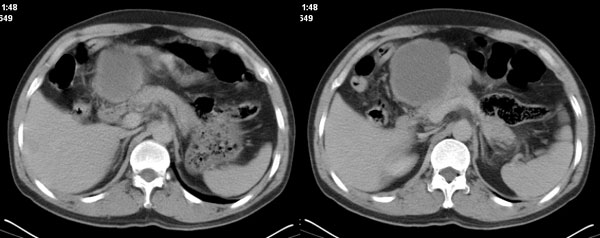

李**,男,46岁,便血1天入院,慢性贫血貌,腹平、软,剑突下压痛,肠鸣音稍活跃,hb大于1g/l,胃镜:慢性浅表性胃炎,b超:1肝内多发性占位 2腹腔内囊性肿块 ,肝内圆形影平扫ct值42.9,动脉期48.6,静脉期58.2,延迟期62.2

影像学表现:1 腹腔前中部、胰腺前方囊实性病灶(个人认为确定有否实性成分存在这是关键,涉及到鉴别诊断,如果是口服阳性造影剂则可明确左侧是不是小肠了),囊性部分囊壁不均,实性部分有强化,与小肠关系较密切,局部小肠受推移;与胰头、胃后壁均有脂肪间隙存在;2 胰腺无异常改变,胰周无渗出;3肝后段包膜下2个小圆形低密度灶,从图像和楼主提供的ct值来看有轻度强化,灶周无片状强化,不似单纯囊肿及肝癌、炎性病变表现;4 腹膜后及腹腔内无淋巴结肿大。

分析:1 如果腹腔内是囊实性病灶,则应多考虑肿瘤性病变,如源于小肠的间叶源性组织如神经源性肿瘤或间质瘤等;如果这么大存在恶性变的可能,那么肝内则可考虑为转移,征象亦符合;这种可能性最大;

2 如果是单纯囊性病灶,则需鉴别于胆总管囊肿、胰腺囊肿、系膜囊肿了;胆总管囊肿应稍偏后,但憩室型胆总管囊肿可呈类似表现,肝内则用多发肝内囊肿来解释也勉强通过--先天性胆管囊肿不能排除;胰腺囊肿需可出现如此部位,但较少,胰腺本身及胰周均无异常,可能性较小;系膜囊肿则不能解释肝内病灶,如果用二种疾病来分开解释则违背了一元论原则。

诊断:小肠间叶组织源性肿瘤如神经源性肿瘤或间质瘤恶性变伴肝内转移可能性最大,不除外先天性胆管囊肿。

胰腺边界清晰,胰周筋膜不厚,胰周脂肪密度无明显增高;其前方囊实性病灶,边界清晰,增强后实性部分轻度强化;肝内多发边界清晰低密度影,增强后无明显强化(平扫ct值42.9,动脉期48.6,静脉期58.2,延迟期62.2)。

考虑:胰腺囊腺瘤,肝内小肝癌可能大。